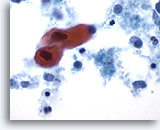

Figure 77

Sputum

Atypical squamous metaplastic cells are considered suspicious for squamous cell carcinoma as their nuclei become hyperchromatic and angulated. 60X

Sputum

Atypical squamous metaplastic cells are considered suspicious for squamous cell carcinoma as their nuclei become hyperchromatic and angulated. 60X

Figure 77

Sputum

Atypical squamous metaplastic cells are considered suspicious for squamous cell carcinoma as their nuclei become hyperchromatic and angulated.

60X

Sputum

Atypical squamous metaplastic cells are considered suspicious for squamous cell carcinoma as their nuclei become hyperchromatic and angulated.

60X